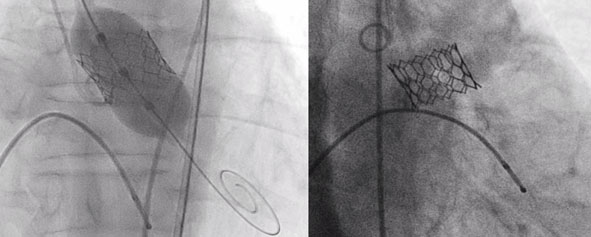

ಮಣಿಪಾಲ, ನ.23: ಮಣಿಪಾಲದ ಕಸ್ತೂರ್ಬಾ ವೈದ್ಯಕೀಯ ಕಾಲೇಜು ಮತ್ತು ಆಸ್ಪತ್ರೆಯ ಹೃದ್ರೋಗ ವಿಭಾಗದ ತಜ್ಞ ವೈದ್ಯರ ತಂಡವೊಂದು ತೆರೆದ ಹೃದಯ ಶಸ್ತ್ರಚಿಕಿತ್ಸೆ ಇಲ್ಲದೇ ಮಹಾಪಧಮನಿಯ ಕವಾಟವನ್ನು ಯಶಸ್ವಿಯಾಗಿ ಬದಲಾಯಿಸಿದೆ.

ಟ್ರಾನ್ಸ್ಕ್ಯಾಥೆಟರ್ ಎರೋಟಿಕ್ ವಾಲ್ವ್ ಇಂಪ್ಲಾಂಟೇಷನ್ (ಟಿಎವಿಐ) ನಂತರ ಕೆಲವೇ ದಿನಗಳಲ್ಲಿ ರೋಗಿ ಗಳನ್ನು ಸ್ಥಿರ ಸ್ಥಿತಿಯಲ್ಲಿ ಆಸ್ಪತ್ರೆಯಿಂದ ಬಿಡುಗಡೆ ಮಾಡಲಾಯಿತು. ಟ್ರಾನ್ಸ್ಕ್ಯಾಥೆಟರ್ ಮಹಾಪಧಮನಿಯ ಕವಾಟದ ಬದಲಾವಣೆಯನ್ನು ದೇಶದ ಕೆಲವೇ ಹೃದ್ರೋಗ ತಜ್ಞರು ಮಾತ್ರ ಮಾಡುತ್ತಾರೆ. ಮಣಿಪಾಲ ಕಸ್ತೂರ್ಬಾ ಮೆಡಿಕಲ್ ಕಾಲೇಜು ಮತ್ತು ಆಸ್ಪತ್ರೆ ಯಲ್ಲಿ ‘ದಿ ಟೀಮ್ ತಾವಿ ’ ಇದುವರೆಗೆ ಇಂತಹ ಅನೇಕ ಚಿಕಿತ್ಸಾ ವಿಧಾನವನ್ನು ಯಶಸ್ವಿಯಾಗಿ ನಡೆಸಿದೆ ಎಂದು ಪ್ರಕಟಣೆ ತಿಳಿಸಿದೆ.

76 ವರ್ಷ ವಯಸ್ಸಿನ ಪುರುಷ ರೋಗಿಯು ಒಂದು ತಿಂಗಳಿನಿಂದ ತೀವ್ರವಾದ ಉಸಿರಾಟದ ತೊಂದರೆಯಿಂದ ಬಳಲುತ್ತಿದ್ದರು. ಇದರ ತೊಂದರೆ ಕ್ರಮೇಣ ಹೆಚ್ಚುತ್ತಿತ್ತು. ಅವರ 2ಡಿ ಎಕೋ ತೀವ್ರವಾದ ಕ್ಯಾಲ್ಸಿಫಿಕ್ ಮಹಾಪಧಮನಿಯ ಸ್ಟೆನೋಸಿಸ್ ಅನ್ನು ತೋರಿಸುತಿತ್ತು. ಇಂಥ ಸಂದರ್ಭದಲ್ಲಿ ಪರಿಧಮನಿಯ ಆಂಜಿಯೋಗ್ರಾಮ್ ಸಾಮಾನ್ಯವಾಗಿತ್ತು. ತೆರೆದ ಹೃದಯ ಶಸ್ತ್ರಚಿಕಿತ್ಸೆಗೆ ರೋಗಿ ಹೆಚ್ಚಿನ ಅಪಾಯವನ್ನು ಹೊಂದಿದ್ದರಿಂದ ನಾವು ಈ ರೋಗಿಗೆ ಟ್ರಾನ್ಸ್ಕ್ಯಾಥೆಟರ್ ಮಹಾಪಧಮನಿಯ ಕವಾಟ ಬದಲಾವಣೆ ಮಾಡಿದೆವು. ಇದು ಕೆಎಂಸಿ ಕೋವಿಡ್ ಯುಗದಲ್ಲಿ ಮಾಡಿದ ಮೊದಲ ತಾವಿ ಚಿಕಿತ್ಸಾ ವಿಧಾನವಾಗಿತ್ತು. ಕೆಲವೇ ದಿನಗಳಲ್ಲಿ ರೋಗಿ ಆರೋಗ್ಯವಂತರಾಗಿ ನಗುನಗುತ್ತಾ ಮನೆಗೆ ಮರಳಿದರು ಎಂದು ತಜ್ಞರ ತಂಡ ತಿಳಿಸಿದೆ.

ಅದೇ ರೀತಿ 72 ವರ್ಷ ವಯಸ್ಸಿನ ಪುರುಷ ರೋಗಿ ತೀವ್ರವಾದ ಉಸಿರಾಟದ ತೊಂದರೆ ಮತ್ತು ತಲೆತಿರುಗುವಿಕೆ ಯಿಂದ ಬಳಲುತ್ತಿದ್ದು ಅವರಿಗೂ ತೆರೆದ ಹೃದಯ ಶಸ್ತ್ರಚಿಕಿತ್ಸೆ ಸಾಧ್ಯವಿರಲಿಲ್ಲ. ಹೀಗಾಗಿ ತಾವಿ ಚಿಕಿತ್ಸಾ ವಿಧಾನದ ಮೂಲಕ ಮಹಾಪಧಮನಿಯ ಕವಾಟವನ್ನು ಬದಲಿಸಲಾಯಿತು. ಕೆಲವೇ ದಿನಗಳಲ್ಲಿ ಅವರನ್ನು ಆಸ್ಪತ್ರೆಯಿಂದ ಬಿಡುಗಡೆ ಮಾಡಲಾಯಿತು.

ಮತ್ತೊಬ್ಬ 74 ವರ್ಷ ವಯಸ್ಸಿನ ಪುರುಷ ರೋಗಿ, ತೀವ್ರ ಹೃದಯ ವೈಫಲ್ಯ ಮತ್ತು ದೀರ್ಘಕಾಲದ ಕೆಮ್ಮಿನಿಂದ ಬಳಲುತ್ತಿದ್ದರು.ಅವರ ಶ್ವಾಸಕೋಶದ ಕಾಯಿಲೆಯನ್ನು ಮೊದಲು ಗುಣಪಡಿಸಿ ಬಳಿಕ ಅವರಿಗೆ ಕವಾಟದ ಬದಲಾವಣೆ ಚಿಕಿತ್ಸೆಯನ್ನು ಯಶಸ್ವಿಯಾಗಿ ನಡೆಸಲಾಯಿತು ಎಂದು ಪ್ರಕಟಣೆ ತಿಳಿಸಿದೆ.

ಮಹಾಪಧಮನಿಯ ಸ್ಟೆನೋಸಿಸ್ ಎಡಭಾಗದ ಹೃದಯ ಕವಾಟದ ಕಿರಿದಾಗುವಿಕೆಯಾಗಿದ್ದು, ಅದು ಇಡೀ ದೇಹಕ್ಕೆ ರಕ್ತ ಪೂರೈಕೆಯಲ್ಲಿ ನಿರ್ಣಾಯಕ ಪಾತ್ರ ವಹಿಸುತ್ತದೆ. ಕೆಲವೊಮ್ಮೆ ಇದು ವಯಸ್ಸಾಗುತ್ತಿದ್ದಂತೆ ಹಾನಿಗೊಳಗಾಗ ಬಹುದು. ಸಾಮಾನ್ಯವಾಗಿ ಇಂತಹ ಹಾನಿಗೊಳಗಾದ ಕವಾಟಗಳನ್ನು ತೆರೆದ ಹೃದಯ ಶಸ್ತ್ರಚಿಕಿತ್ಸೆಯಿಂದ ಬದಲಾಯಿಸಲಾಗುತ್ತದೆ. ಆದರೆ ತೀವ್ರ ಮಹಾಪಧಮನಿ ಸ್ಟೆನೋಸಿಸ್ ರೋಗಿಗಳಲ್ಲಿ ಇದು ಅಪಾಯ ಒಡ್ಡುವ ಸಾಧ್ಯತೆ ಹೆಚ್ಚಿದ್ದು, ಇಂತಹ ರೋಗಿಗಳಿಗೆ ಶಸ್ತ್ರಚಿಕಿತ್ಸೆಯಿಲ್ಲದೆ ಕವಾಟವನ್ನು ಬದಲಿಸುವುದು ಉತ್ತಮ ಆಯ್ಕೆ ಎಂದು ಡಾ ಟಾಮ್ ದೇವಾಸಿಯಾ ತಿಳಿಸಿದರು.

ಹೃದ್ರೋಗ ತಜ್ಞ, ಹೃದಯ ರಕ್ತನಾಳದ ಶಸ್ತ್ರಚಿಕಿತ್ಸಕ, ಅರಿವಳಿಕೆ, ಕ್ಯಾಥ್ಲ್ಯಾಬ್ ಮತ್ತು ಐಸಿಯು ತಂಡ ಸೇರಿದ ತಾವಿಯ ಸಂಪೂರ್ಣ ತಂಡ ತಾವಿಗೆ ಒಳಗಾದ ಪ್ರತೀ ಅಸ್ವಸ್ಥ ರೋಗಿಗಳ ಜೀವನದಲ್ಲಿ ನಿರ್ಣಾಯಕ ಪಾತ್ರವನ್ನು ವಹಿಸಿದೆ ಮತ್ತು ಈ ರೋಗಿಗಳಿಗೆ ಹೊಸ ಜೀವನವನ್ನು ನೀಡುವಲ್ಲಿ ಪ್ರಮುಖ ಪಾತ್ರ ವಹಿಸಿದೆ ಎಂದು ಕೆಎಂಸಿಯ ವೈದ್ಯಕೀಯ ಅಧೀಕ್ಷಕ ಡಾ ಅವಿನಾಶ್ ಶೆಟ್ಟಿ ತಿಳಿಸಿದ್ದಾರೆ.